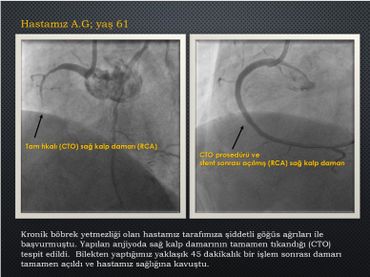

Anjiyo görüntülerinizi analiz edilmesini ve tedaviniz için ideal yöntemin ne olacağını öğrenmek ister misiniz!